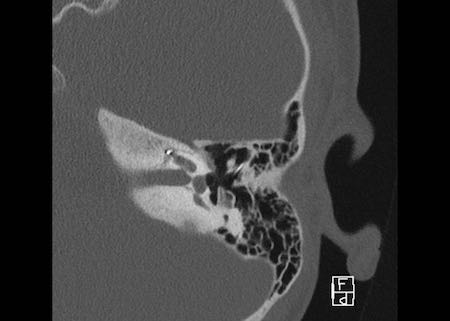

Bên trái là hình ảnh của một bé gái 2 tuổi.

Các hình ảnh từ kết quả chụp CT được thực hiện trước khi cấy ốc tai điện tử.

Quan sát thấy dị dạng nhẹ ở đỉnh ốc tai – không có sự phân tách giữa vòng thứ hai và vòng thứ ba, và trụ ốc tai xương vắng mặt.

Cống tiền đình bình thường.